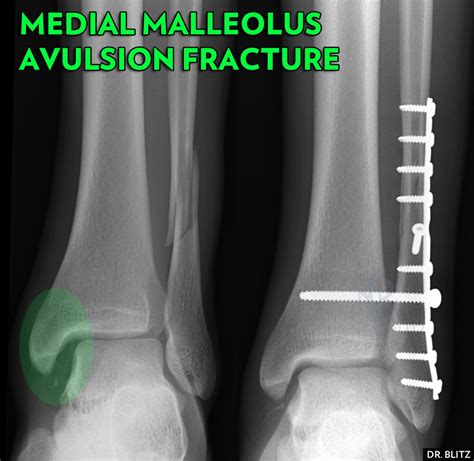

• X-Rays: X-rays are the primary imaging tool used to confirm the presence and extent of the fracture.

• Open Reduction and Internal Fixation (ORIF): A procedure where the bone fragments are realigned and held in place with screws, plates, or rods.